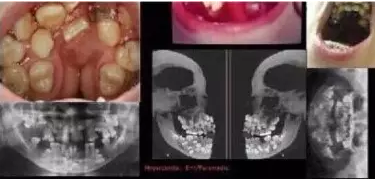

多生牙可以出现在牙弓的任何部位,不过最常见于恒牙,位置一般在上颌牙弓的前牙。其次常发生在上颌牙弓和下颌牙弓的第四颗磨牙。这些多生牙看上去就像多出来的阻生智齿。多出来的上颌牙弓的前牙叫做正中多生牙,多出来的第四颗磨牙称之为远中磨牙。出生或出生以后多生的乳牙叫诞生牙。

多生牙的发生率一般占总人口的1%~4%,患病的男女比例为2:1,大多数情况是多出1颗牙齿。曾经出现过多例有30颗多生牙的病例,但是这种现象极为罕见。如果被诊断出多颗多生牙,此人一般会颌骨发育不良,且与皮肤弹性过度综合征、魏纳-加德娜综合征及唇腭裂症等相关。

对多生牙进行及早发现、评估和治疗非常重要,因为多出的牙齿会对病患的面部外形和生理功能产生影响。大部分的多生牙都会在临床解决,其治疗方法通常是尽可能地去除多余的牙齿。多生牙可能造成临近牙齿的生长延迟或者造成牙列的异常拥挤,通常需要矫正治疗。如果任其发展,多生牙可能会导致囊肿或者肿瘤的发生。